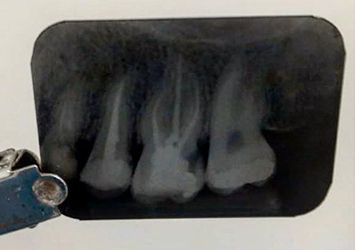

A película digital representa uma avanço no diagnóstico onde as imagens são obtidas com maior qualidade e rapidez proporcionando ao profissional uma imagem mais detalhada dos canais radiculares, além de um tempo de exposição menor.